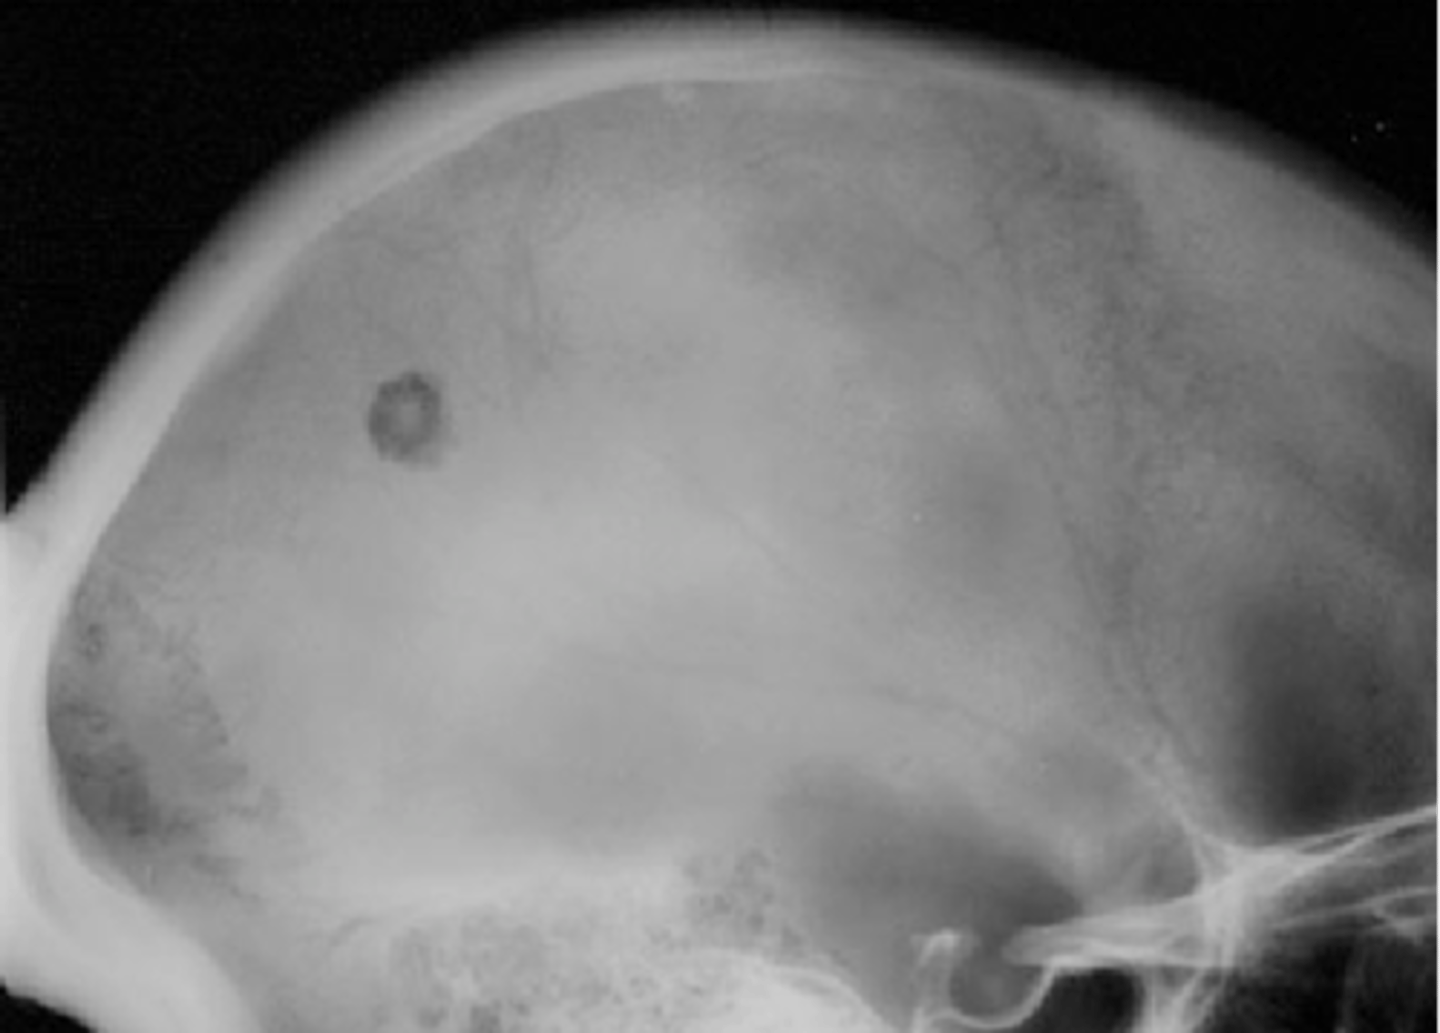

Beveled edge

ID radiographic feature of eosinophilic granuloma in the skull

<p>ID radiographic feature of eosinophilic granuloma in the skull</p>

74

New cards

Button sequestrum